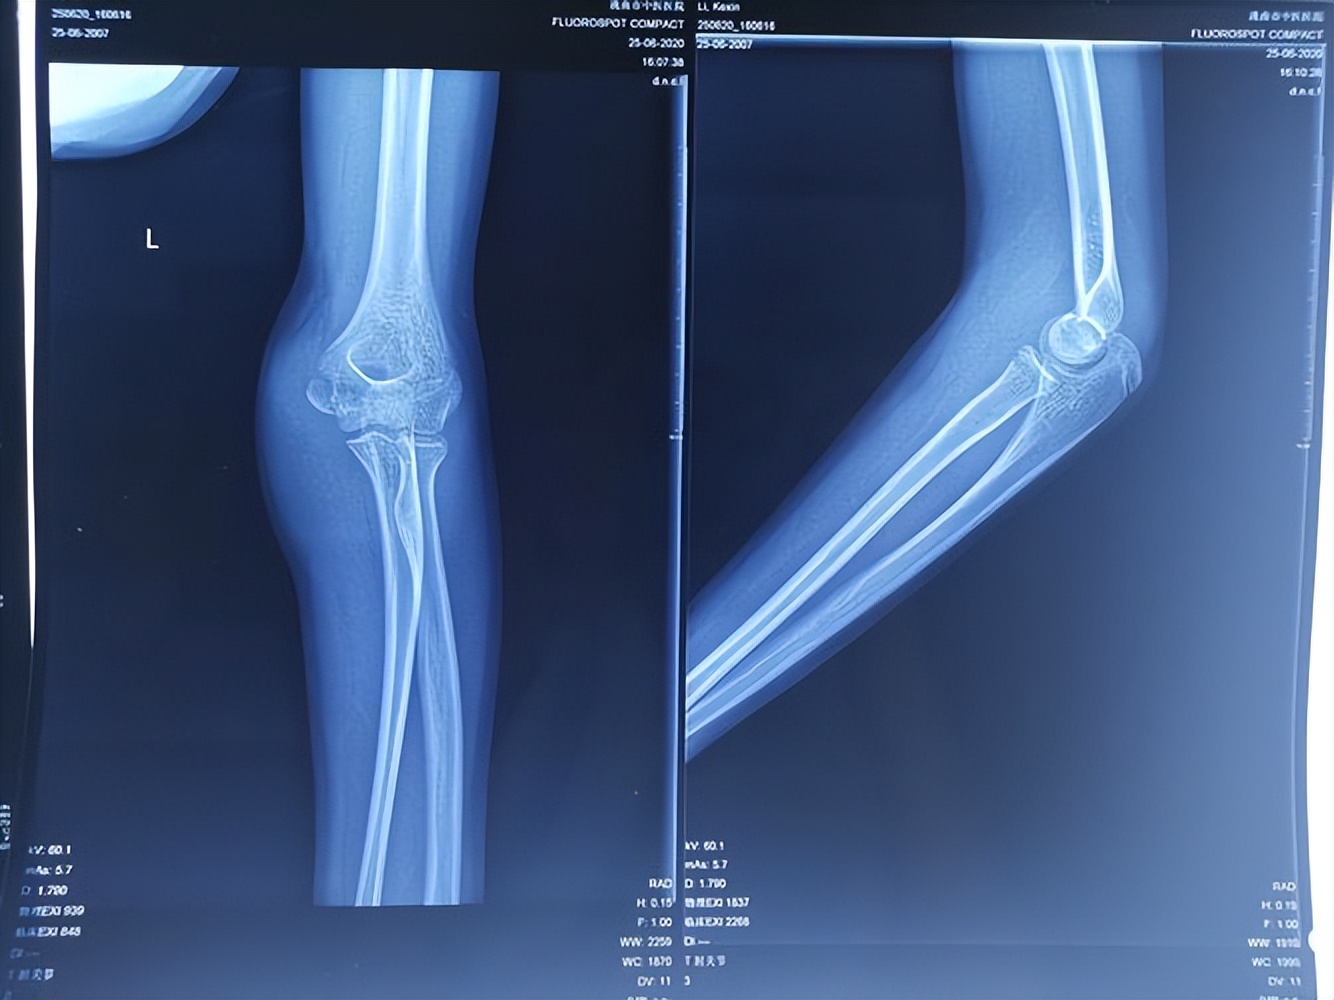

直角架固定时髋关节屈曲60°,是考虑为学龄前儿童股骨干骨折多为中上段骨折,股骨干上1/3骨折,骨折近端受髂腰肌、臀中、小肌和外旋肌的牵拉而呈屈曲、外展和外旋畸形 ,中1/3骨折断端重叠移位,远端受内收肌牵拉而内翻畸形。

由于股骨干骨折直角架固定时采取屈髋60°屈膝90°体位, 直角架的大腿托板部分对大腿产生垂直于托板的向上的作用力,与患肢大腿部重力共同产生沿大腿纵轴方向的作用于骨折近端的持续牵引的合力。

由于伤肢膝关节屈曲90°臀部稍微悬空,骨折近端的持续牵引的合力在直角架膝关节处产生作用于骨折远端纵轴方向的对抗牵引合力 。牵引力和反牵引力共同作用能解除伤侧大腿的肌肉痉挛,恢复肢体内部动力平衡,有利于维持骨折断端的对位对线。